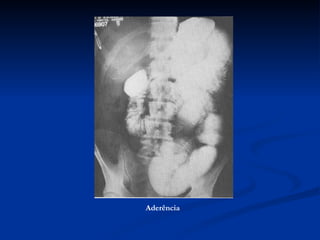

Aderência